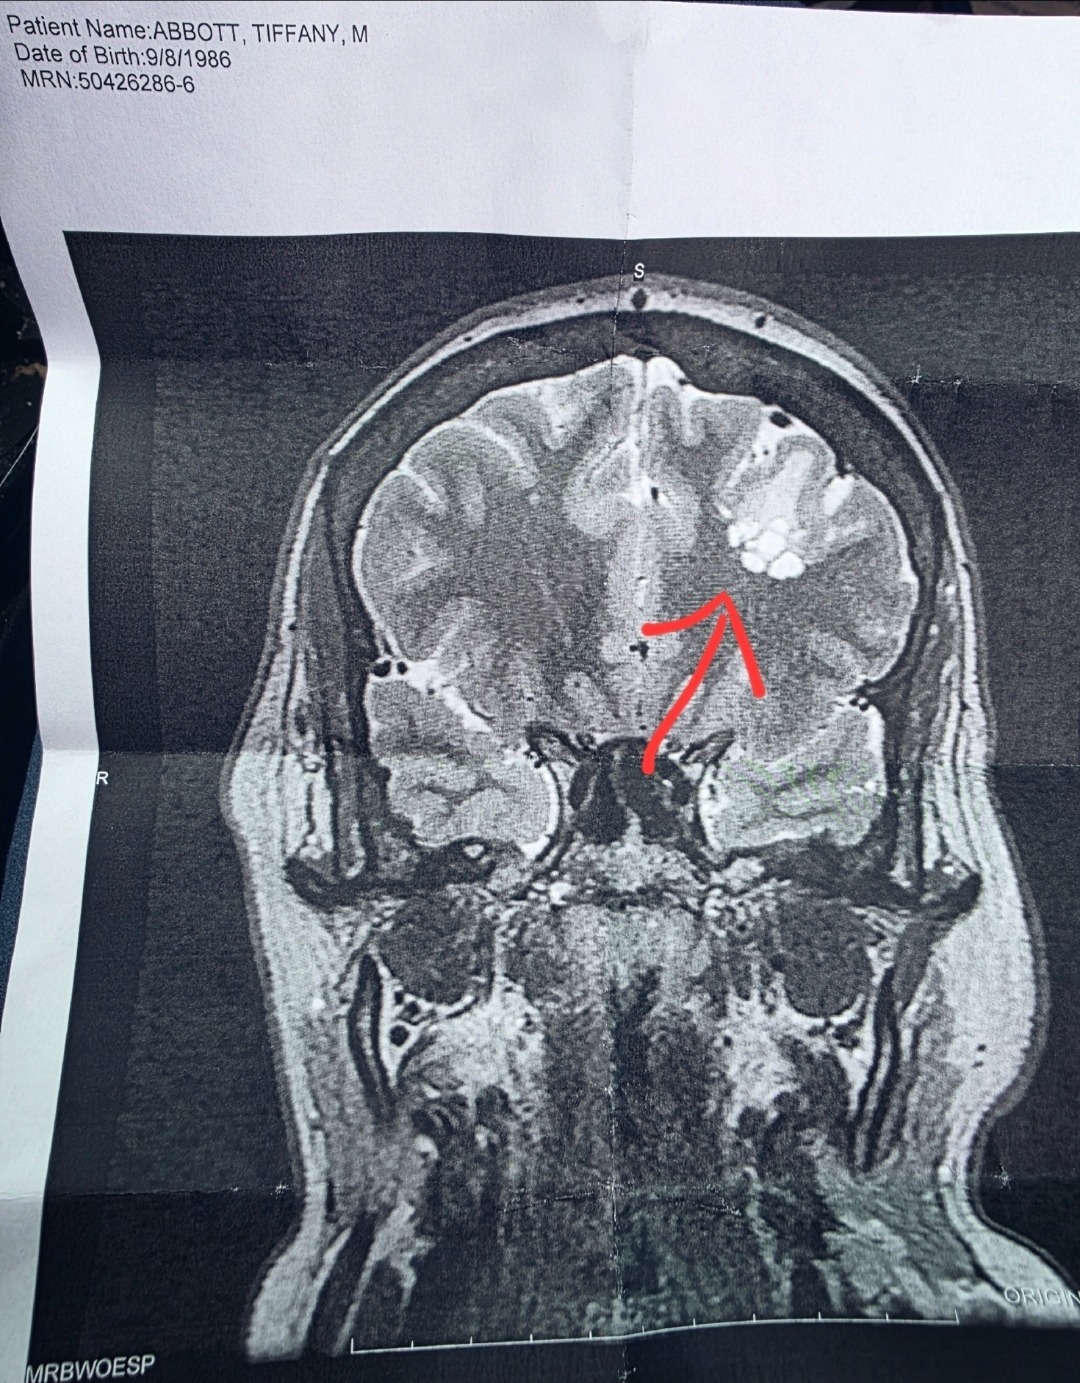

In 2022, after a bad slip and fall, doctors discovered that I have a brain tumor almost the size of a lime. That’s when my journey with seizures and epilepsy began. Over time, the seizures have only gotten worse. I have a few different kinds, and last October I nearly lost my life after suffering 7 or 8 grand mal seizures in a row. I was rushed to the Dartmouth ICU, put in a medically induced coma, and diagnosed with something called "status epilepticus" —an emergency condition where seizures just wouldn't stop.